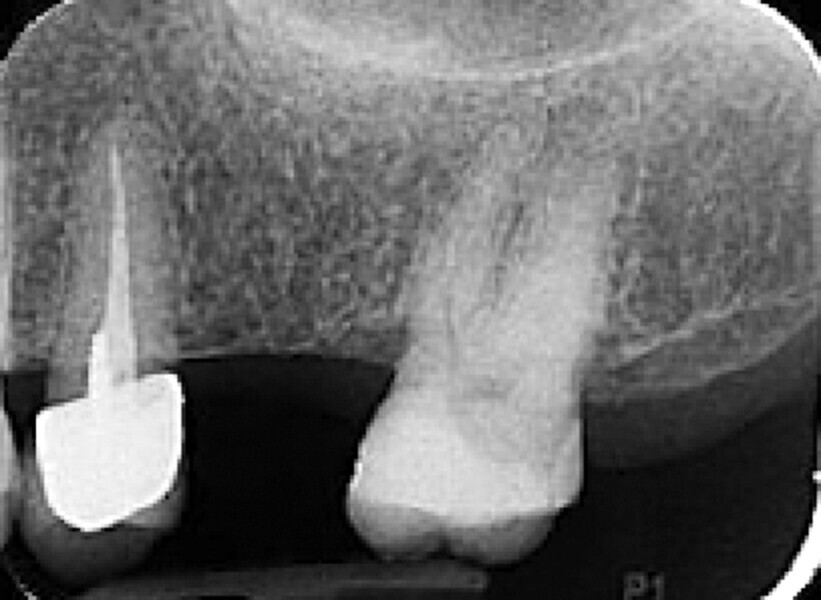

Fig. 35 : Région molaire édentée avant l’implantation.

Fig. 36 : Région molaire édentée avant l’implantation.

Un patient présentant un défaut infraosseux s’est présenté au cabinet dentaire avec le souhait explicite d’un traitement par un implant en zircone, pour remplacer l’une de ses molaires. Un implant deux pièces en zircone a donc été posé et le défaut infra-osseux a été traité dans le même temps, au moyen d’une allogreffe osseuse et du dérivé de matrice amélaire Emdogain (Straumann). La mise en charge n’a pas été réalisée à ce stade (Figs. 35–45).